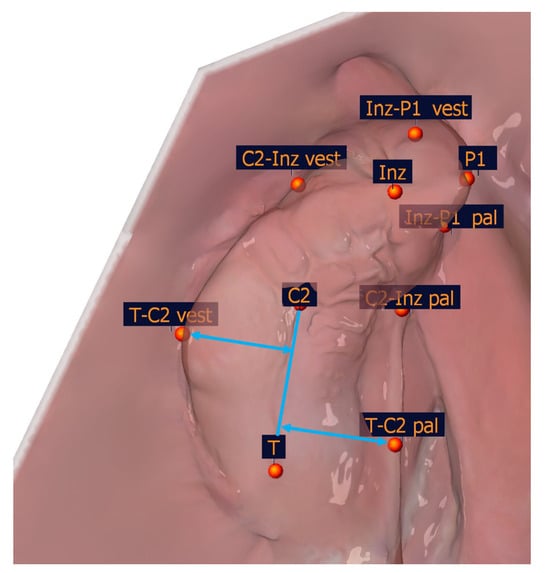

The selection of the measuring points detailed in Table 1 was based on a number of factors, including the publications of Mazaheri et al. [18], Ashley-Montagu [19], Sillman [20], and Robertson [21]. If a point appears on both jaw segments, a ′ indicates that the point is located on the smaller jaw segment. Figure 4 and Table 1 show the measuring points on a dental left-sided cleft lip and palate model.

To identify the transversal landmarks, the large and small segments were divided into the subsegments (T-C2, C2-Inz, and Inz-P1 for the large segment and P2-C2′ and C2′-T′ for the small segment). The most vestibular and most palatal points in each section were determined (Table 2, Figure 5).

Figure 4. Illustration of the anatomical measuring points. The anatomical measuring points and their description are presented in Table 1.